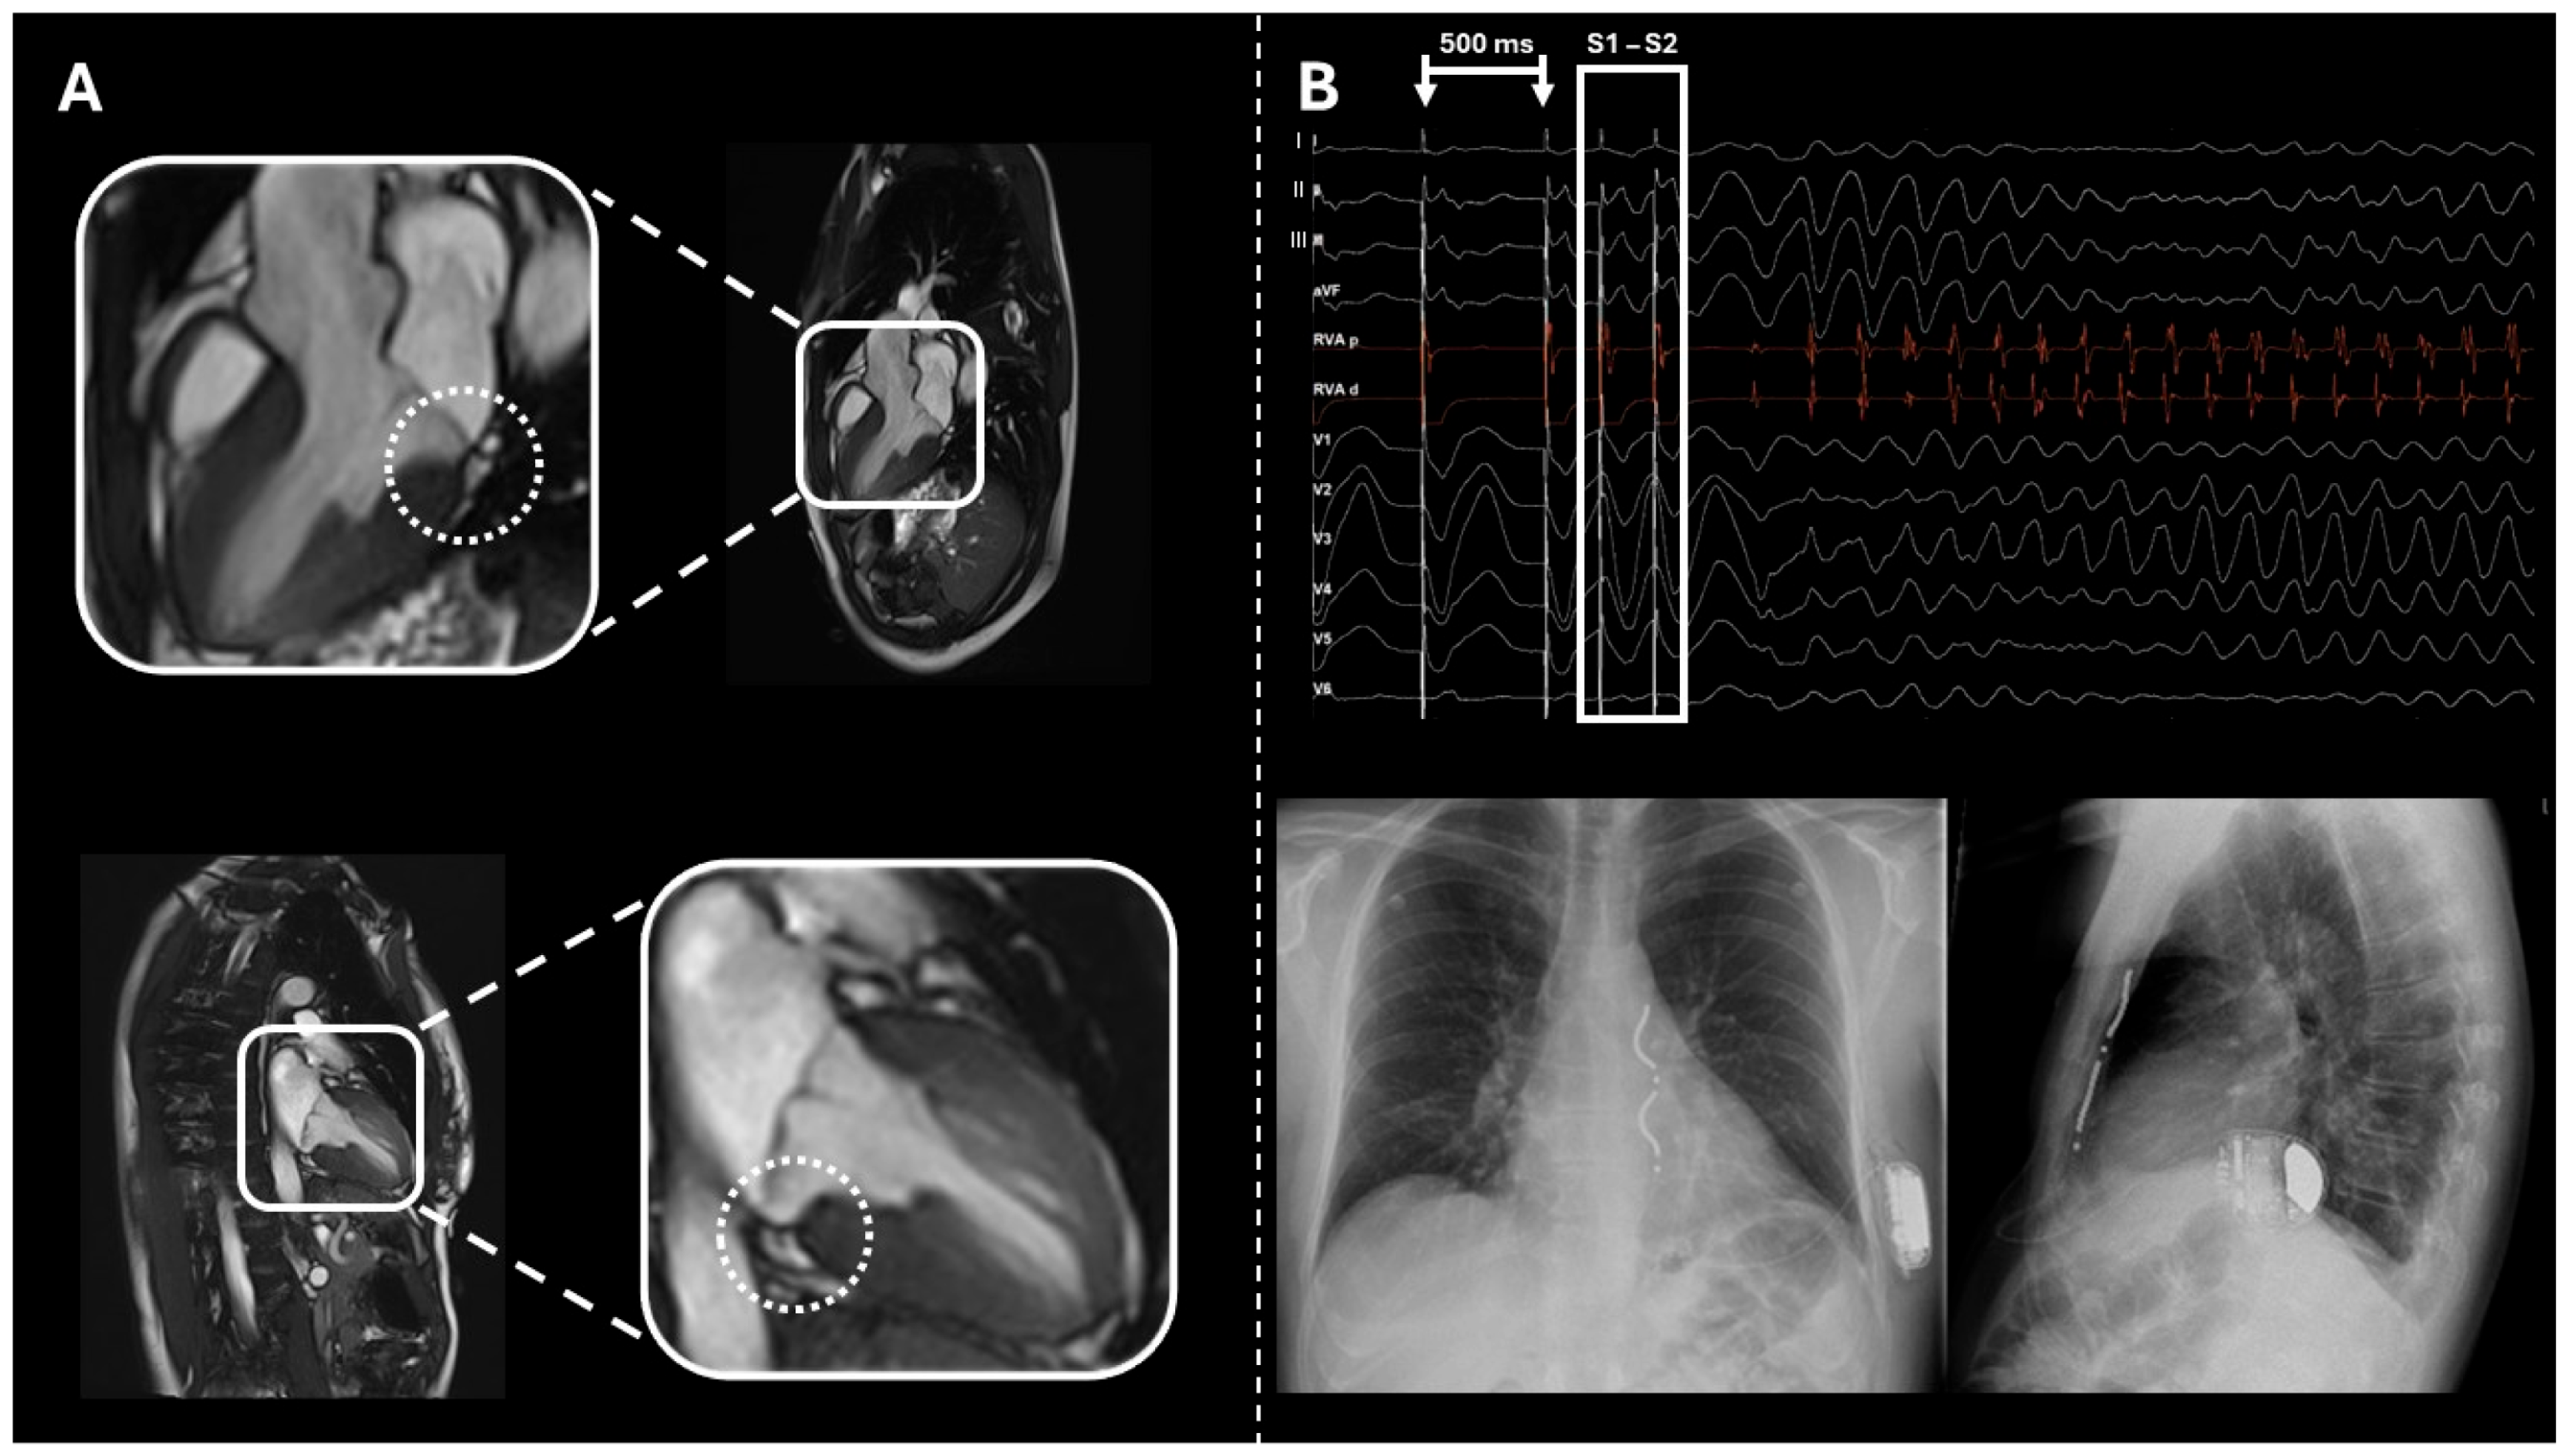

2.4. Case 4